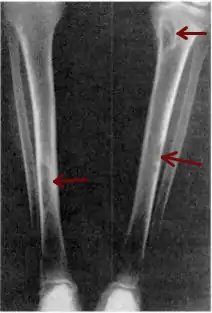

| Osteitis fibrosa cystica of the tibia. Arrows point to the brown tumors which are typically present in bones of people with OFC. | |

Osteitis fibrosa cystica (/ˌɒstiˈaɪtɪs faɪˈbroʊsə ˈsɪstɪkə/ OSS-tee-EYE-tis fy-BROH-sə SIS-tik-ə) is a skeletal disorder resulting in a loss of bone mass, a weakening of the bones as their calcified supporting structures are replaced with fibrous tissue (peritrabecular fibrosis), and the formation of cyst-like brown tumors in and around the bone. Osteitis fibrosis cystica (OFC), also known as osteitis fibrosa, osteodystrophia fibrosa, and von Recklinghausen's disease of bone (not to be confused with von Recklinghausen's disease, neurofibromatosis type I), is caused by hyperparathyroidism, which is a surplus of parathyroid hormone from over-active parathyroid glands. This surplus stimulates the activity of osteoclasts, cells that break down bone, in a process known as osteoclastic bone resorption. The hyperparathyroidism can be triggered by a parathyroid adenoma, hereditary factors, parathyroid carcinoma, or renal osteodystrophy. Osteoclastic bone resorption releases minerals, including calcium, from the bone into the bloodstream, causing both elevated blood calcium levels, and the structural changes which weaken the bone. The symptoms of the disease are the consequences of both the general softening of the bones and the excess calcium in the blood, and include bone fractures, kidney stones, nausea, moth-eaten appearance in the bones, appetite loss, and weight loss.

X-rays may also be used to diagnose the disease. Usually, these X-rays will show extremely thin bones, which are often bowed or fractured. However, such symptoms are also associated with other bone diseases, such as osteopenia or osteoporosis.[29] Generally, the first bones to show symptoms via X-ray are the fingers.[22] Furthermore, brown tumors, especially when manifested on facial bones, can be misdiagnosed as cancerous.[29] Radiographs distinctly show bone resorption and X-rays of the skull may depict an image often described as "ground glass" or "salt and pepper".[30][31] Dental X-rays may also be abnormal.[2]

Cysts may be lined by osteoclasts and sometimes blood pigments, which lend to the notion of "brown tumors." Such cysts can be identified with nuclear imaging combined with specific tracers, such as sestamibi.[3] Identification of muscular degeneration or lack of reflex can occur through clinical testing of deep tendon reflexes, or via photomotogram (an achilles tendon reflex test).[24][32]

The brown tumors commonly associated with OFC display many of the same characteristics of osteoclasts.[23] These cells are characteristically benign, feature a dense, granular cytoplasm, and a nucleus that tends to be ovular in shape, enclosing comparatively fine chromatin. Nucleoli also tend to be smaller than average.[18]